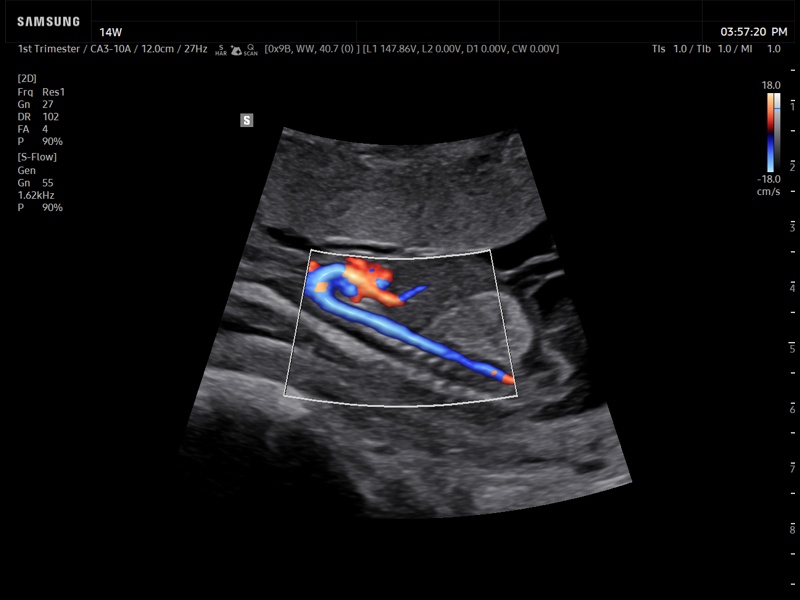

Fetal aorta, S-Flow™ (echogramm №935)

[RU] Ultrasound image №935: Fetal aorta in S-Flow™ mode (1-st trimester, convex probe 3-10 MHz).

Echogramm was received by ultrasound scanner Z20 (new model).